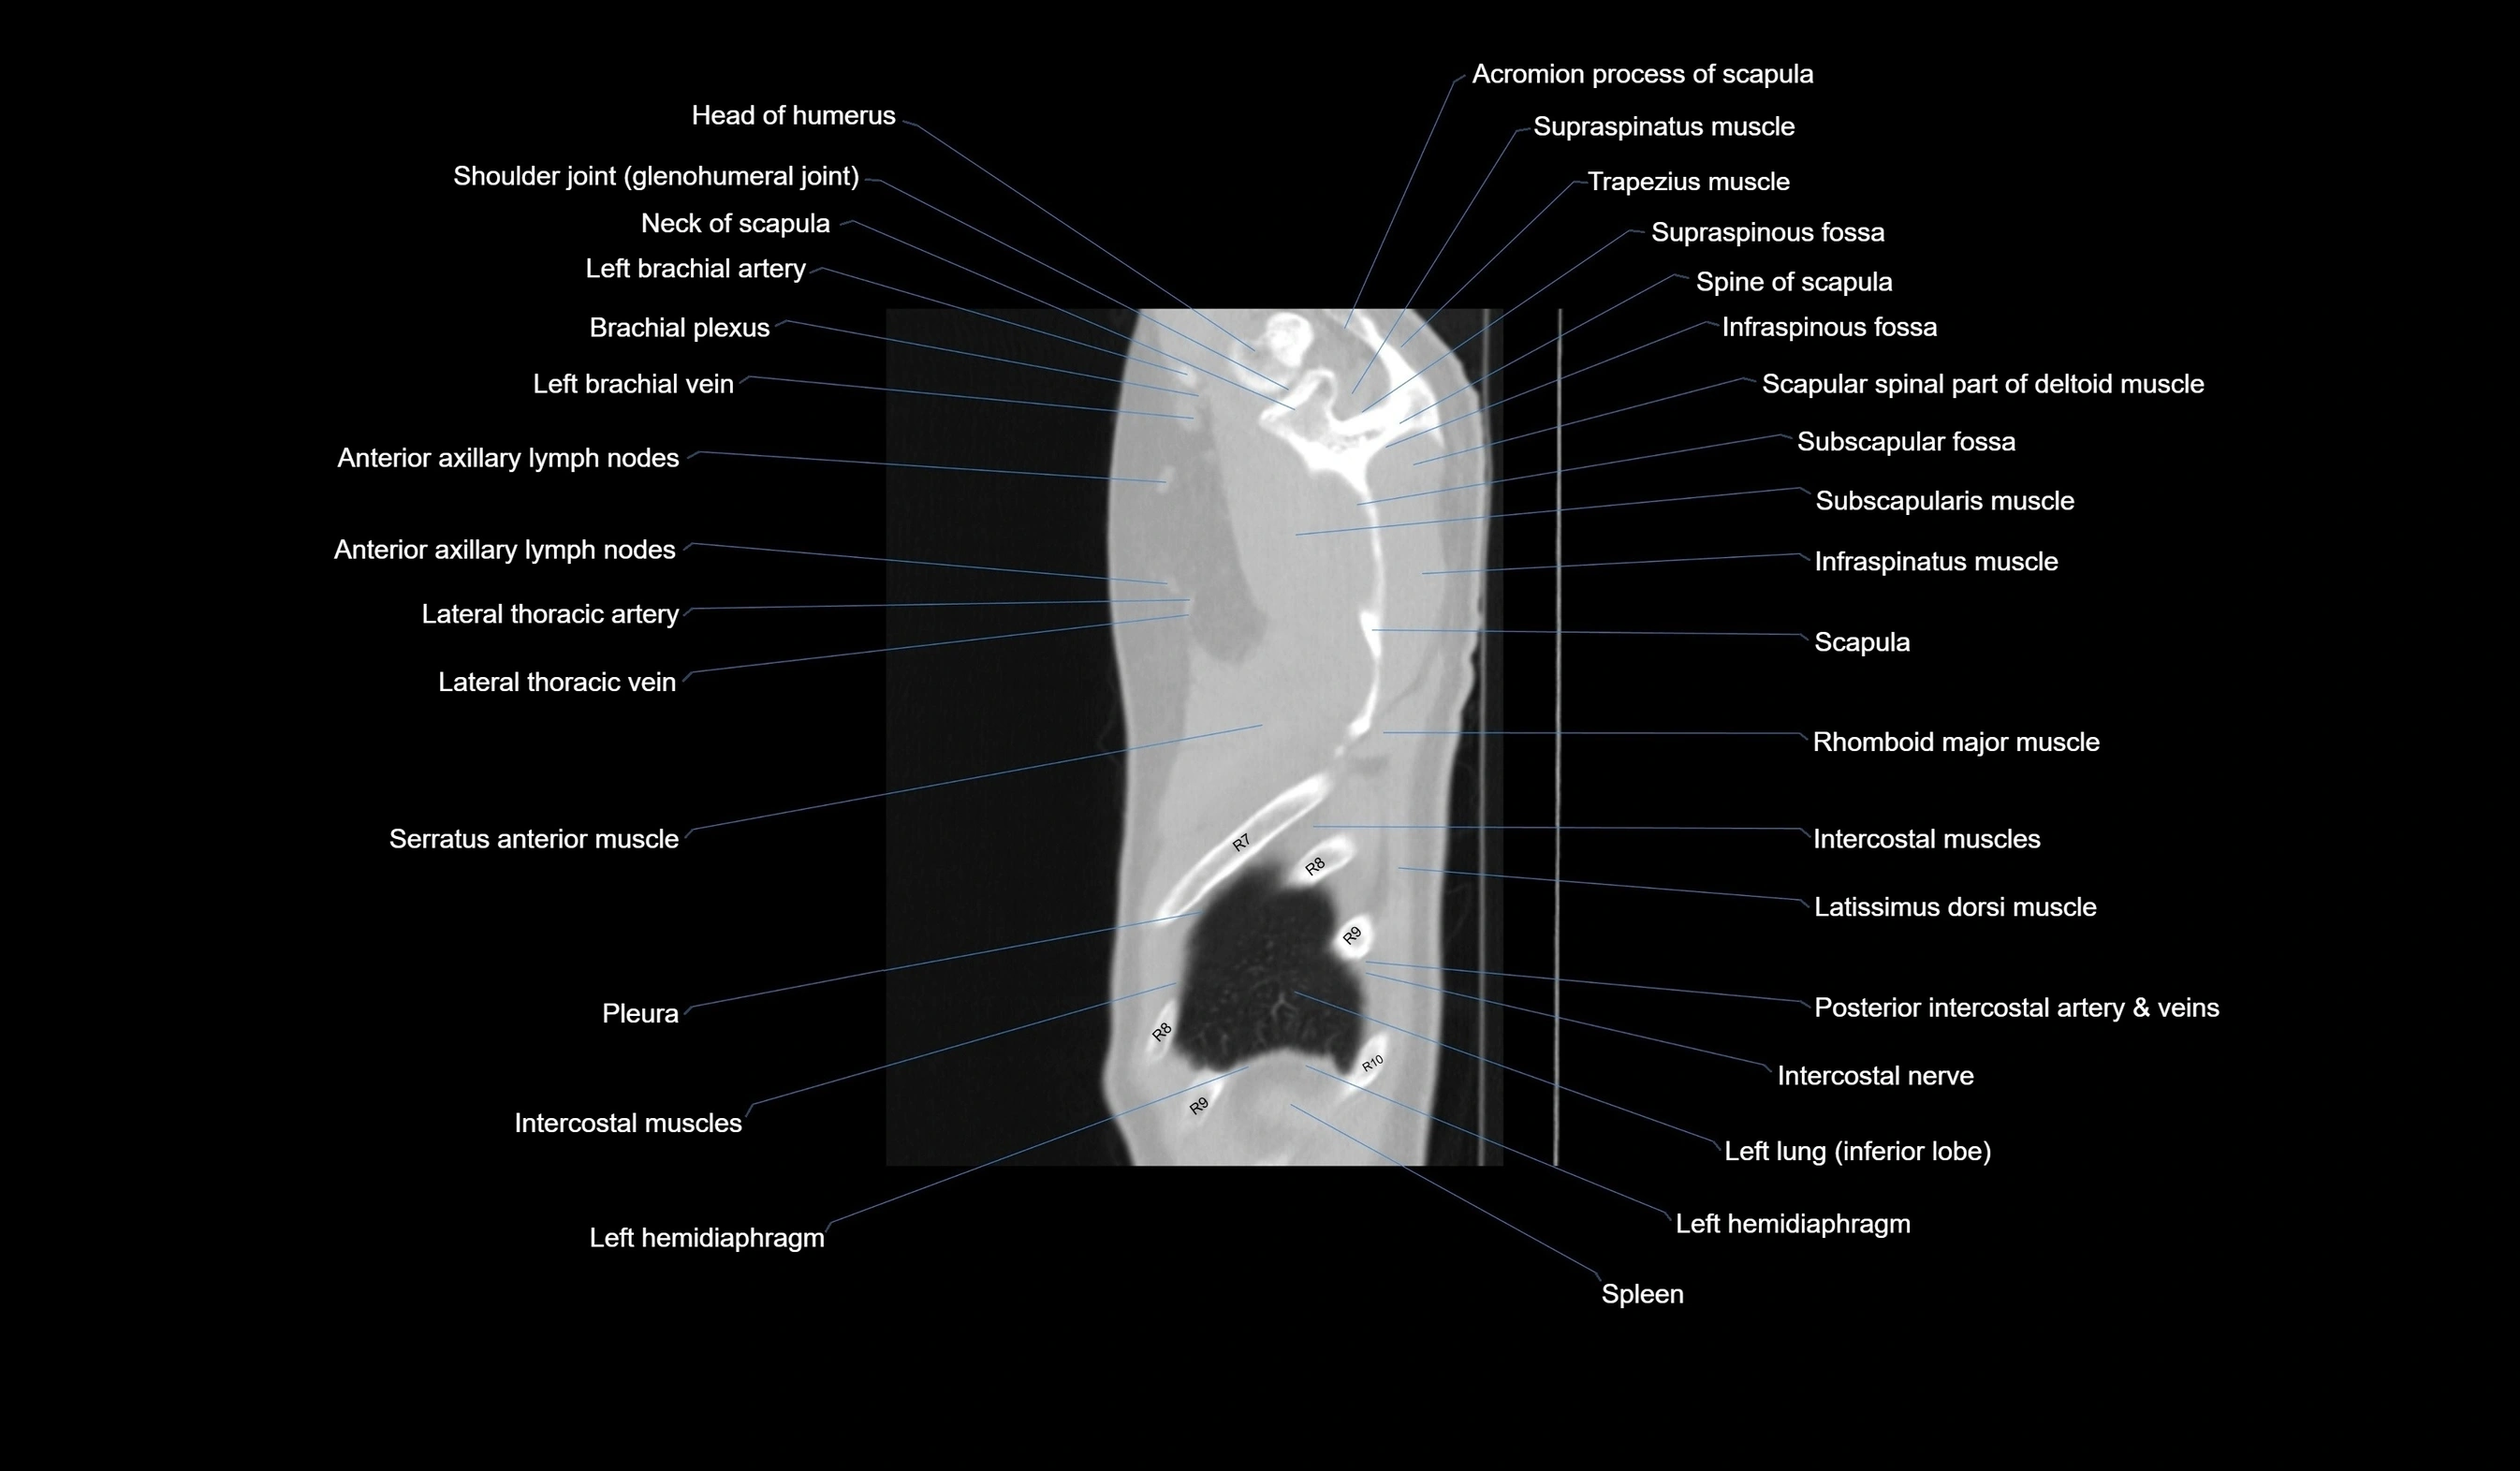

CT images